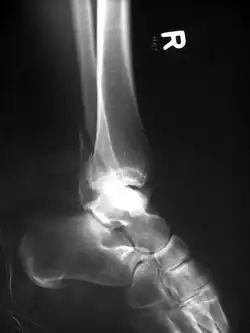

Das Verfahren wird chirurgisch nur bei Brüchen eingesetzt, die in Gelenken verlaufen und deren Bruchstücke unter Zugspannung von Sehnen stehen, so dass der Muskelzug die Bruchstücke zwangsläufig voneinander entfernt. Solche Brüche entstehen daher auch bei Stürzen immer durch eine Kombination aus direkter Krafteinwirkung auf den Knochen und durch die einwirkende Zugspannung der Muskulatur. Typische Beispiele für solche Brüche sind die Querfrakturen des Ellenhakens und der Kniescheibe durch Sturz oder Anprall auf den Ellenbogen und aufs Knie mit entsprechender Muskelanspannung zur Abwehr des Sturzes. Man könnte sehr eingeschränkt auch die Abrisse am Innen- und Außenknöchel des oberen Sprunggelenkes und an der Basis des 5. Mittelfußknochens sowie am Tuberkulum majus des Oberarmknochens zu diesen Abrissfrakturen zählen und sie auch mit einer Drahtschlinge behandeln. Eine echte Zuggurtungswirkung entsteht dabei nicht.

-

Klassische Zuggurtung einer Patellafraktur -

Erweiterte Zuggurtung einer Patellafraktur (mit K-Drähten) -

Eine Bimalleolarfraktur im seitlichen Röntgenbild … -

… und von vorne … -

… mit Zuggurtung am Innenknöchel und Platte am Außenknöchel versorgt